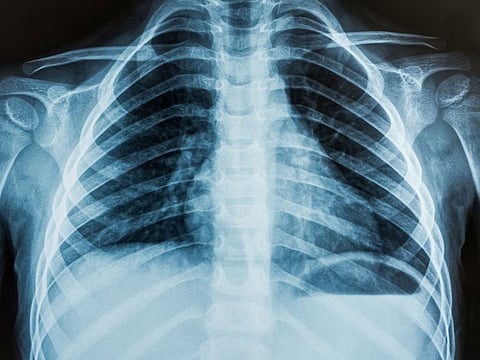

Sydney: Australian researchers have developed an artificial intelligence (AI) system that can rapidly detect Covid-19 from chest X-rays with more than 98 per cent accuracy, and may be more beneficial than the currently used RT-PCR test.

"The new AI system could be particularly beneficial in countries experiencing high levels of Covid-19 where there is a shortage of radiologists. Chest X-rays are portable, widely available and provide lower exposure to ionising radiation than CT scans," he said.

The new AI system, detailed in a paper published in the journal Scientific Reports, uses a deep learning-based algorithm called a Custom Convolutional Neural Network (Custom-CNN) that is able to quickly and accurately distinguish between Covid-19 cases, normal cases, and pneumonia in X-ray images.